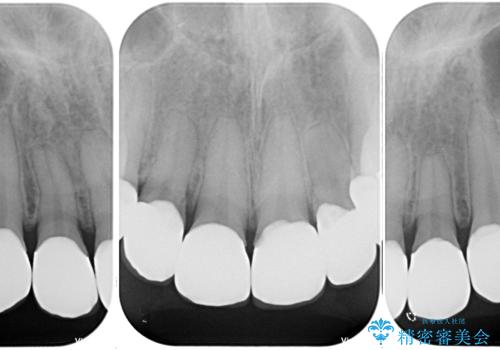

- 前歯の色味が気になるとのことで来院された患者様です。今までに保険のプラスチック(コンポジットレジン)で虫歯の治療をしており経年的な劣化により着色が目立つようになっていました。また歯と歯の隣り合っているところに段差もあり虫歯になっているところもあったため前歯6本のオールセラミッククラウンによる治療を行うこととなりました。

拡大鏡視野下で保険のプラスチック(コンポジットレジン)、虫歯を除去し、オールセラミッククラウンに適した形にしました。

今後は奥歯の治療に取り掛かっていく予定です。